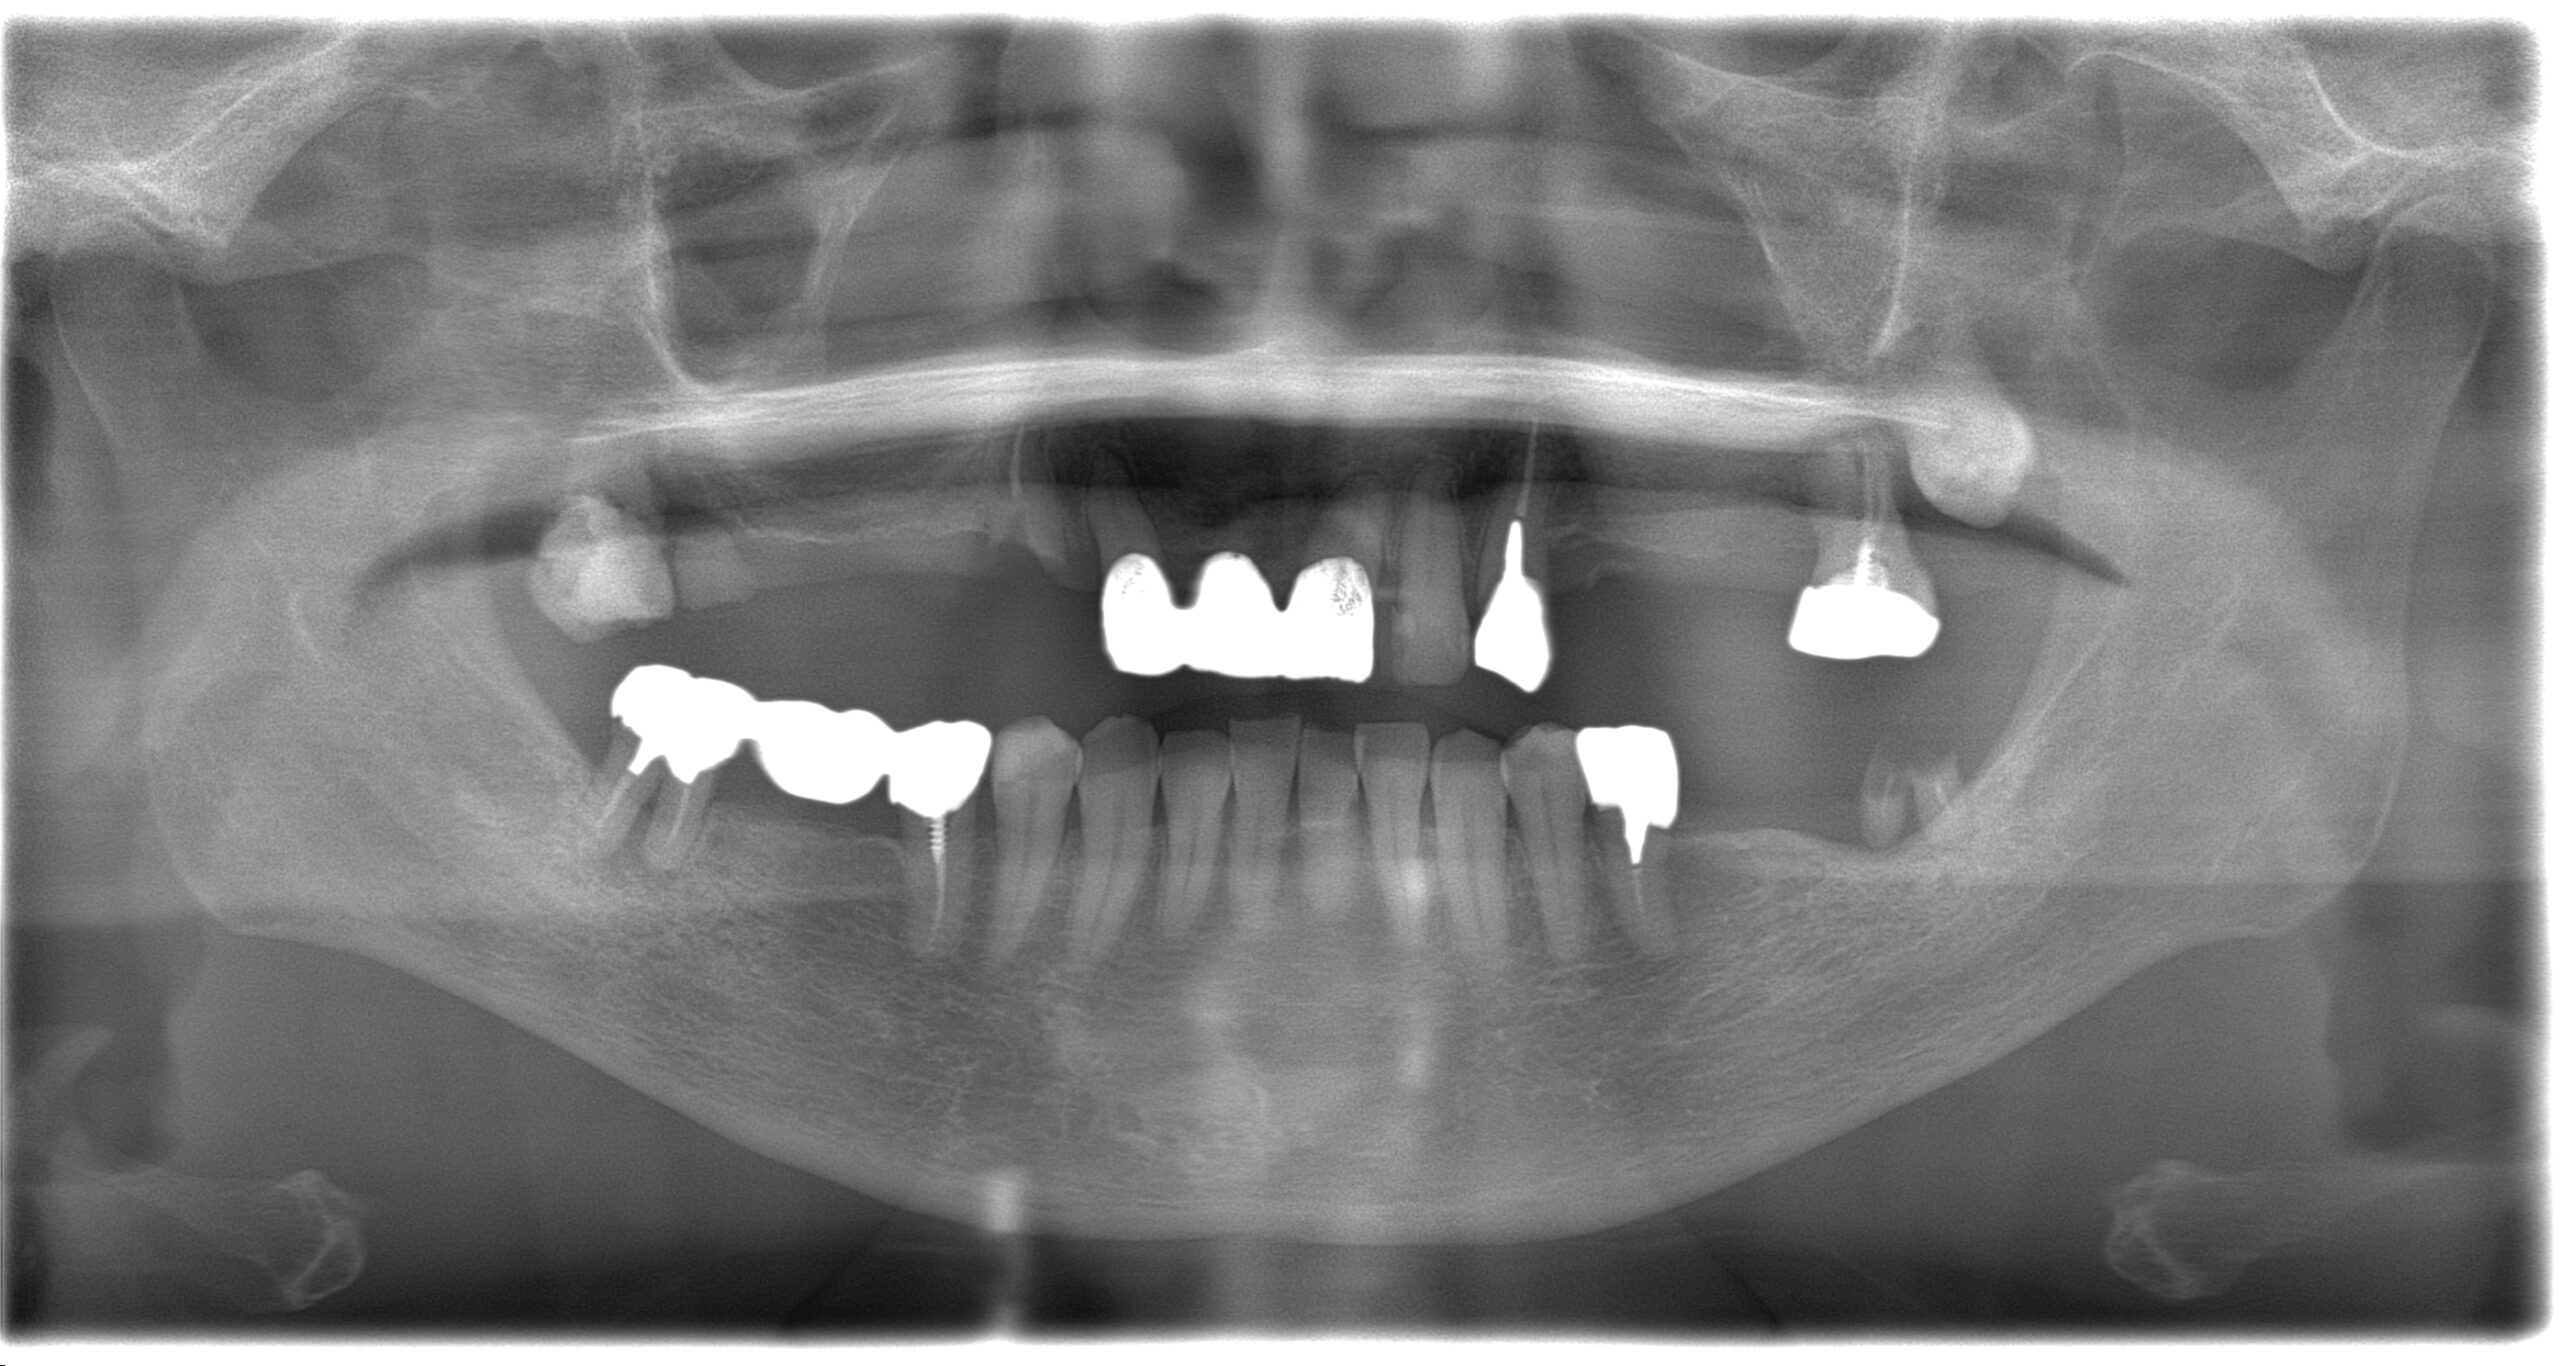

BEFORE

AFTER

主訴

全体的に見た目を綺麗にしたい。奥歯でしっかり噛みたい。

診断名・主な症状

臼歯部欠損

年齢

70歳

治療内容

インプラント埋入(右上4・6,左上4・6,右下6,左下6)

ジルコニアBr(右上3―左上3)

ジルコニア(右下5,左下5)

治療期間/

通院回数

インプラント 1年5ヶ月/13回

ジルコニアBr、ジルコニアクラウン 3ヶ月/10回

費用

インプラント: 2,552,000円

その他治療: 640,000円

合計 3,192,000円

*いずれも税込